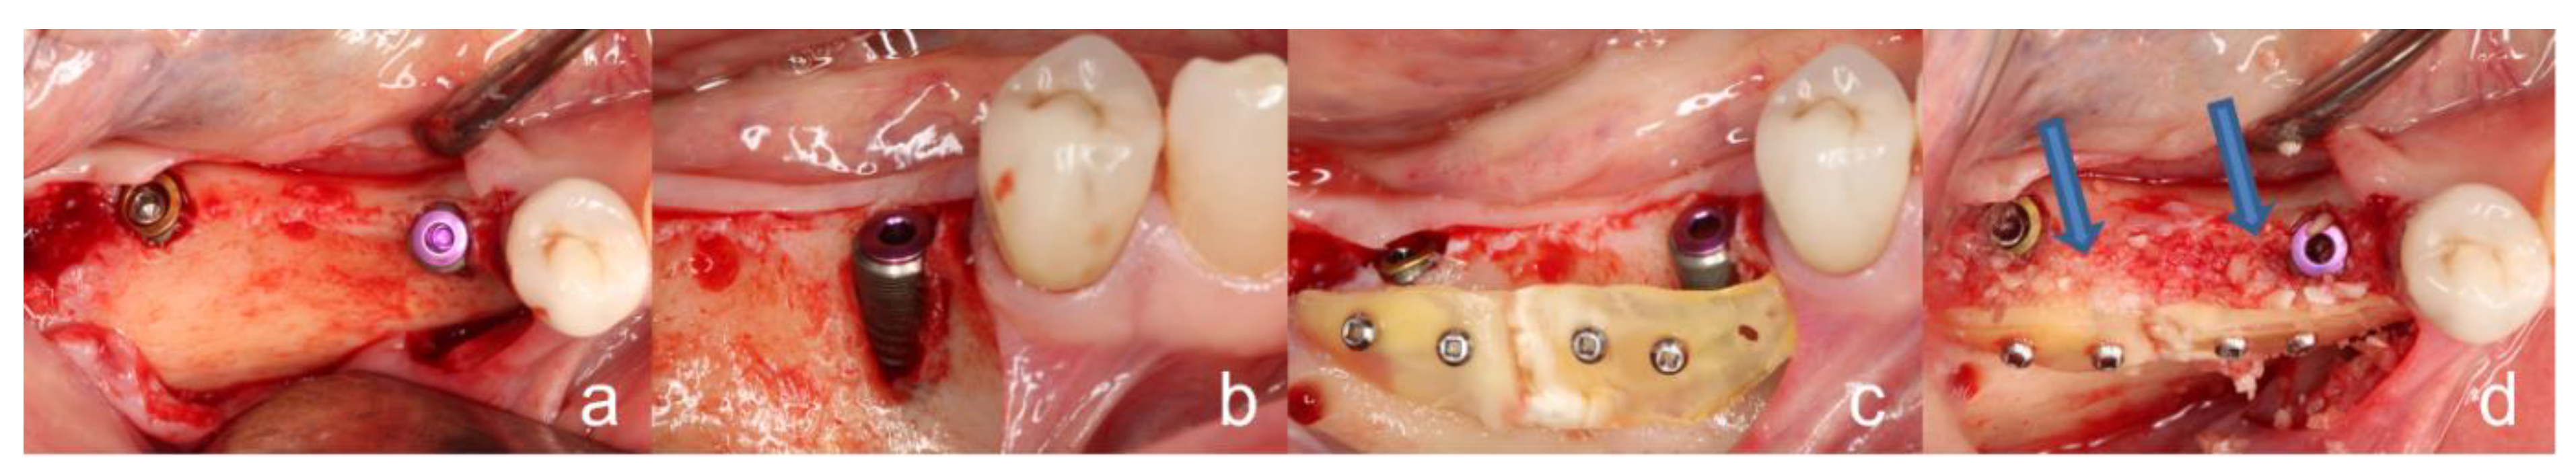

2.4. Surgical Procedure of the Tooth Shell Technique (TST)

2.3. Clinical Procedure of the Tooth Processing

4.2. Non-Severe Complications